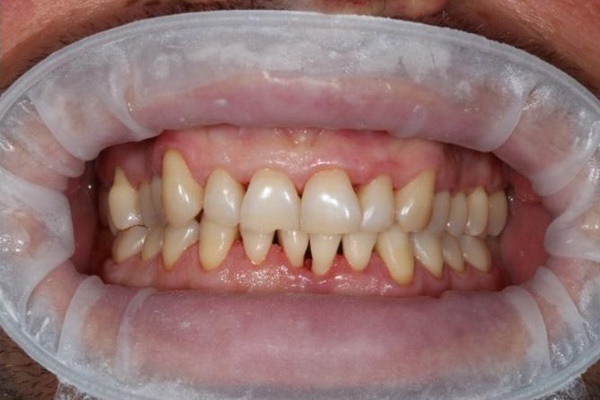

Стан ясен та зубів через 14 місяці після лікування (до та після проведення планової професійної гігієни ротової порожнини).

Не зважаючи на недостатньо якісну індивідуальну гігієну ротової порожнини ясна зберігають природній колір та незначно кровоточать при зондуванні.